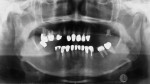

Her dental history included a complete-mouth rehabilitation with a recent replacement of multiple anterior restorations (Figure 1). Her failing restorations had become extensive due to recurrent caries and structural compromises. Six months prior to her initial examination, teeth Nos. 6 and 13 had fractured at the gingival level due to secondary caries (Figure 2).

An intraoral examination revealed generalized failing metal-ceramic and cast gold crowns due to rampant recurrent caries. Early loss of periodontal attachment around several teeth and generalized gingivitis were noted. The edentulous areas of the maxillary left and mandibular right segments presented with Seibert Class I and Class III residual ridge deficiencies, respectively.17,18 In addition, a skeletal and dentoalveolar Angle Class II malocclusion with bimaxillary protrusion was observed. Radiographic analysis indicated short roots, residual root tips, recurrent caries, and highly pneumatized maxillary sinuses (Figure 4). The patient’s progressing medical condition produced a xerostomic oral milieu and had affected her dexterity. This significantly contributed to the development of recurrent caries. In addition, the progression of the tightness and rigidity of her orbicularis oris muscles limited access for dental treatment.